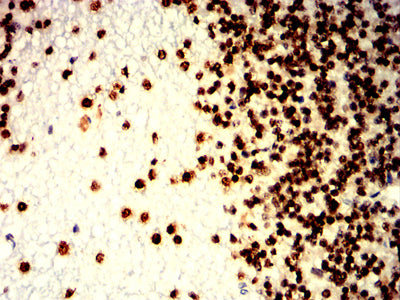

Immunohistochemical analysis of paraffin-embedded human cerebellum tissues using H2AFX mouse mAb with DAB staining.